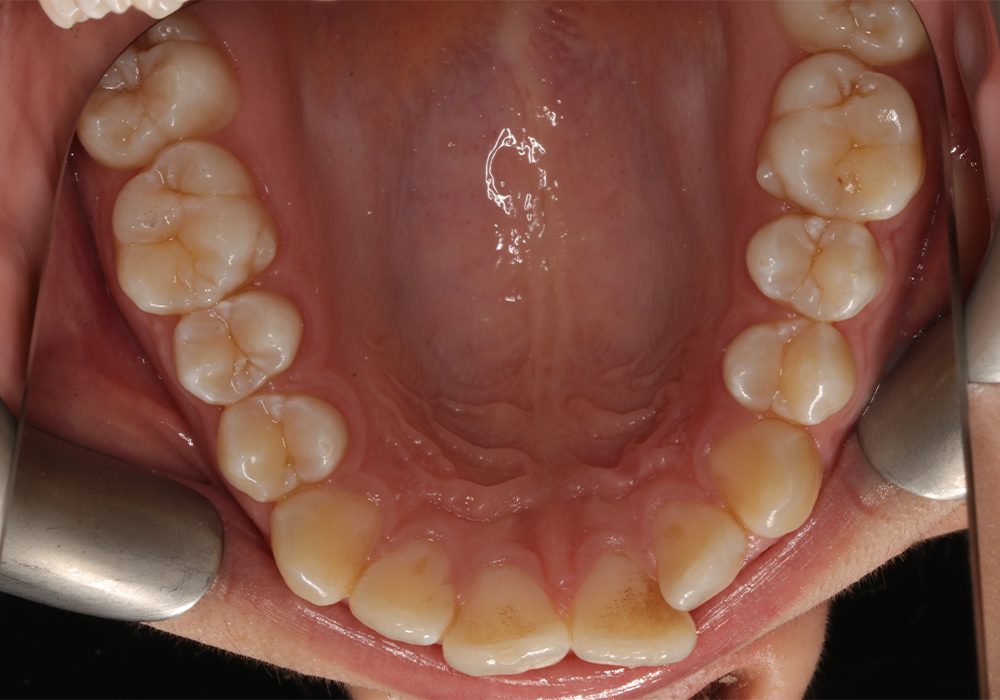

Po copy

Po